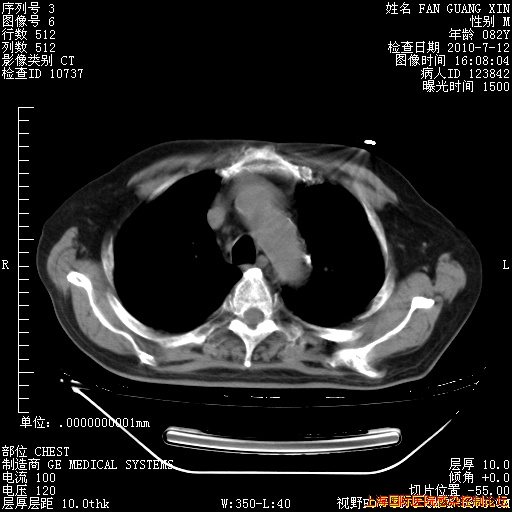

今天复查CT

今天CT

整整相隔30天的肺部CT好像有所好转啊。甲强龙减量第3天,需要观察体温。

海管,自昨日你和我通完话后,不知您岳父消化道症状有无缓解?体温怎样?阅读7.12日胸部ct,个人认为目前激素治疗是有效的,甲强龙减量是适宜的。因在抗痨治疗,需密切观察肝功、肾功能和血常规。不过,老年、长期住院和大量使用激素,很担心菌群失调发生